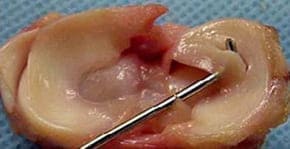

Glucosamina y condroitina ayudan a fortalecer el cartílago, tendones y ligamentos, reducir la inflamación y el edema, y activar la regeneración del cartílago.